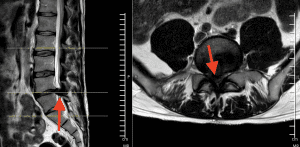

La resonancia magnética (RM) es la herramienta más efectiva para evaluar la médula espinal y las estructuras circundantes. Esta prueba permite obtener imágenes detalladas de los nervios y tejidos blandos, facilitando la identificación de hernias discales, tumores y otras causas de compresión.

Resonancia magnética que muestra una hernia masiva en la región L5-S1, destacada con flechas rojas, ocupando el canal medular casi en su totalidad.